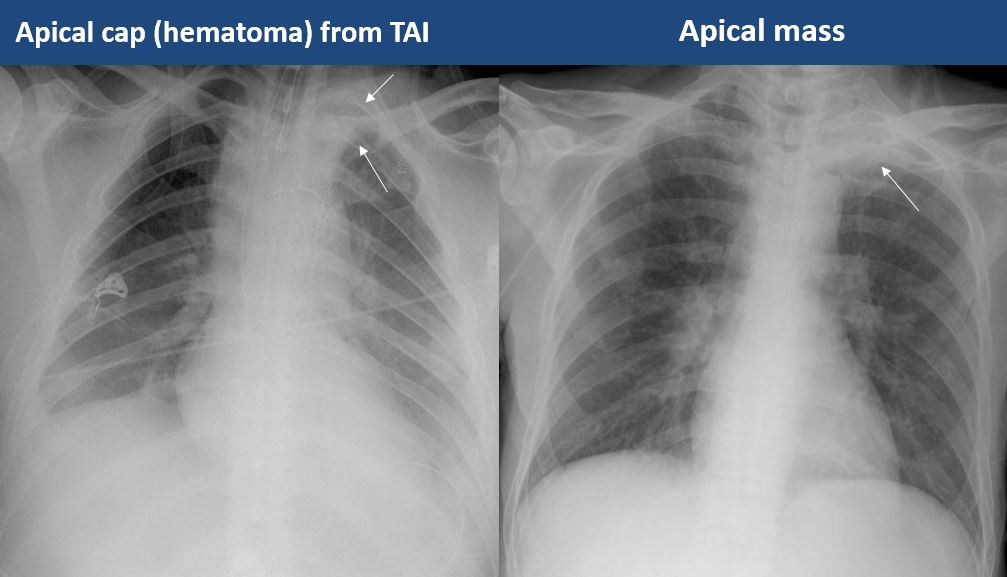

There is asymmetric pleural thickening or capping of the apices. [Yes/No]